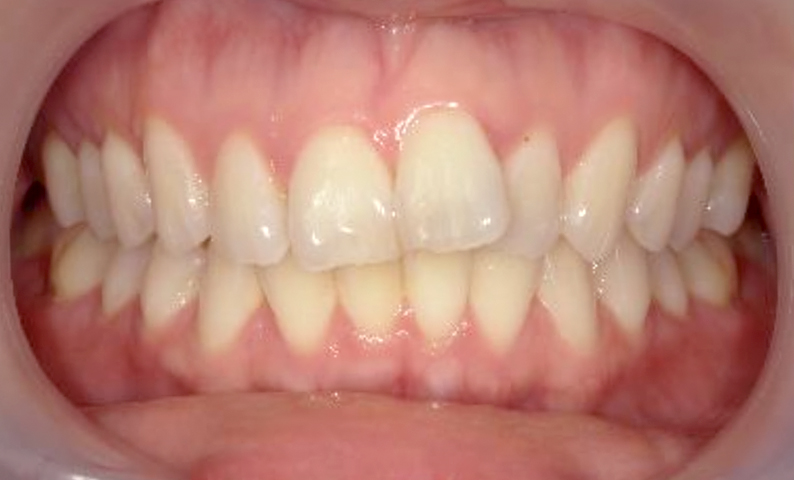

症例_007 前歯「捻転歯」症例

治療期間:10ヶ月金額:30万円+税20代女性少しのねじれ上の前歯だけ

| Before | After |